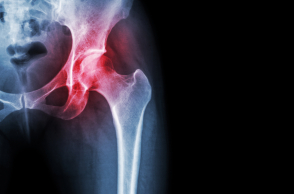

Τα οστεοπορωτικά κατάγματα συνήθως εκδηλώνονται στο ισχίο, τη σπονδυλική στήλη, το βραχίονα ή το αντιβράχιο (πήχυς). Μπορεί όμως να εκδηλωθούν και σε οποιοδήποτε άλλο οστό (λ.χ. πύελο, πλευρές, κνήμη κ.λπ.). Η εκτίμηση της σκελετικής υγείας συνήθως συμπεριλαμβάνει το τεστ εκτίμησης κίνδυνου εμφάνισης κατάγματος (γνωστό ως «μοντέλο FRAX» για τον ελληνικό πληθυσμό). Με τη μέθοδο αυτή υπολογίζεται ο απόλυτος κίνδυνος που έχει ένα άτομο να υποστεί ένα κάταγμα τα επόμενα 10 έτη. Αναλόγως με την ηλικία ή τους παράγοντες κινδύνου του ατόμου, ο θεράπων ιατρός μπορεί να προτείνει μέτρηση της οστικής πυκνότητας.

Η τεχνική που χρησιμοποιείται για την μέτρηση της οστικής πυκνότητας είναι η DXA (μέθοδος διπλής ενεργειακής απορρόφησης). Πρόκειται για μια ταχεία, μη επεμβατική μέθοδο χαμηλής ακτινοβολίας, που υπολογίζει την οστική πυκνότητα συνήθως στην περιοχή του ισχίου και της σπονδυλικής στήλης. Σύμφωνα με τα αποτελέσματα ένα άτομο χαρακτηρίζεται οστεοπορωτικό, οστεοπενικό ή φυσιολογικό. Αυτό καθορίζεται ανάλογα με την απόκλιση του εξεταζόμενου από μια μέση προκαθορισμένη τιμή που αφορά τον υγιή πληθυσμό.

Τα οστεοπορωτικά κατάγματα συχνά έχουν καταστροφικές συνέπειες, ενώ έχουν και τεράστιο κοινωνικο-οικονομικό κόστος. Όπως αναφέρει εκ μέρους της Ελληνικής Ενδοκρινολογικής Εταιρείας ο ενδοκρινολόγος Γεώργιος Τροβάς, από το Εργαστήριο Έρευνας Παθήσεων του Μυοσκελετικου Συστήματος «Θ. Γαροφαλίδης» του ΕΚΠΑ, το 20-24% των ασθενών με κάταγμα ισχίου πεθαίνουν μέσα στον πρώτο χρόνο από την εκδήλωσή του, το 33% χρειάζονται νοσηλεία κατ' οίκον επί τουλάχιστον ένα χρόνο και το 40% δεν ανακτούν την ικανότητα ανεξάρτητης βάδισης.